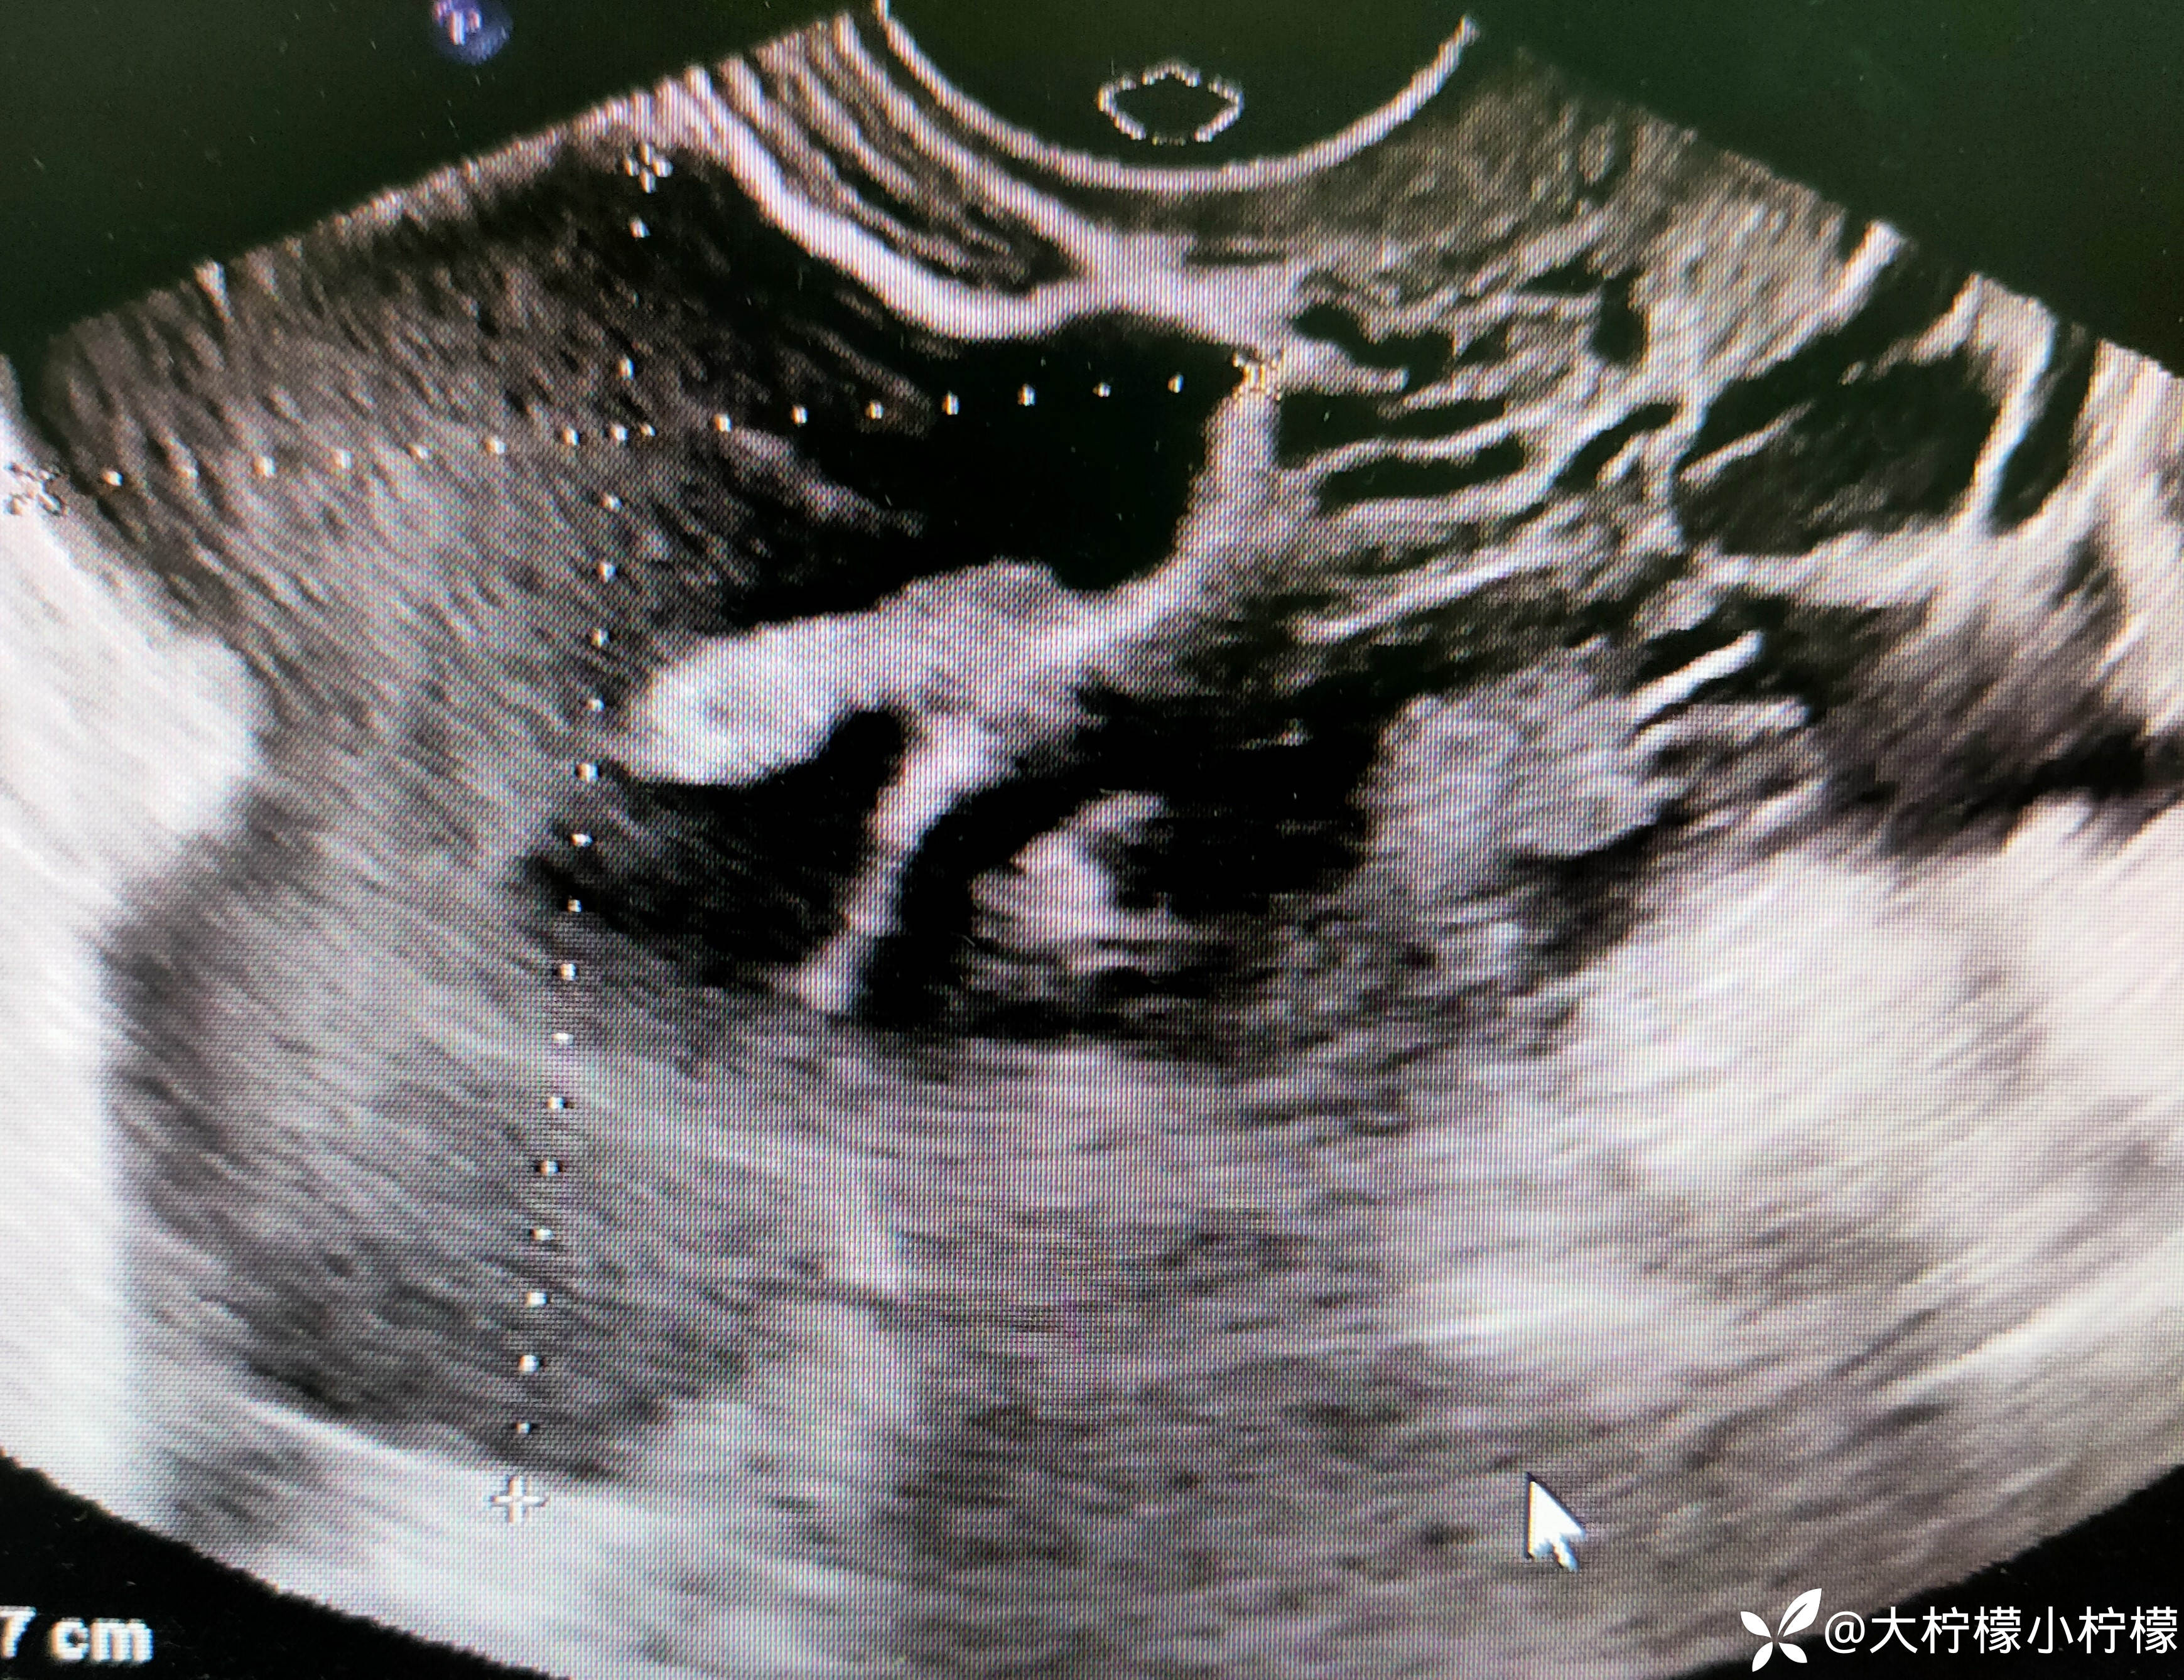

简要病史:患者年轻女性,平素月经周期规律,6-7/30余天,末次月经2023年10月16日,月经量正常,有痛经史,8小时前同房后出现左侧下腹部疼痛,呈持续,急诊超声:如下:

腹腔积液。